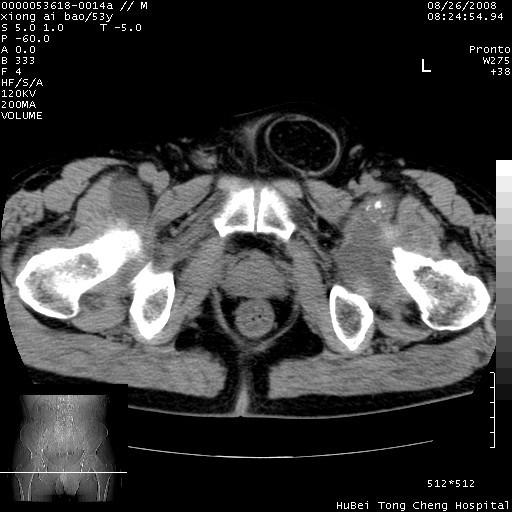

标题: CT15583:M,53Y。请老师指教分析骨盆及其他病变。 [打印本页]

标题: CT15583:M,53Y。请老师指教分析骨盆及其他病变。

股骨头坏死/腹股沟疝。

双侧股骨头无菌坏死,左侧腹股沟斜疝。

非常典型病例,双侧股骨头坏死伴双髋关节周围软组织肿胀,左腹股沟疝。

双侧股骨头坏死伴双髋关节周围软组织肿胀,左腹股沟疝。

双侧骨股头无菌性坏死,左侧腹股沟疝

双侧髋关节肿胀明显,感觉还不能排除结核。

考虑双侧髋关节结核,左侧腹股沟疝